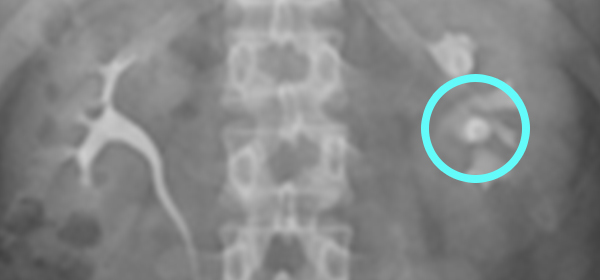

°æÁ¤¸Æ½Å¿ìÁ¶¿µ¼ú (IVP)